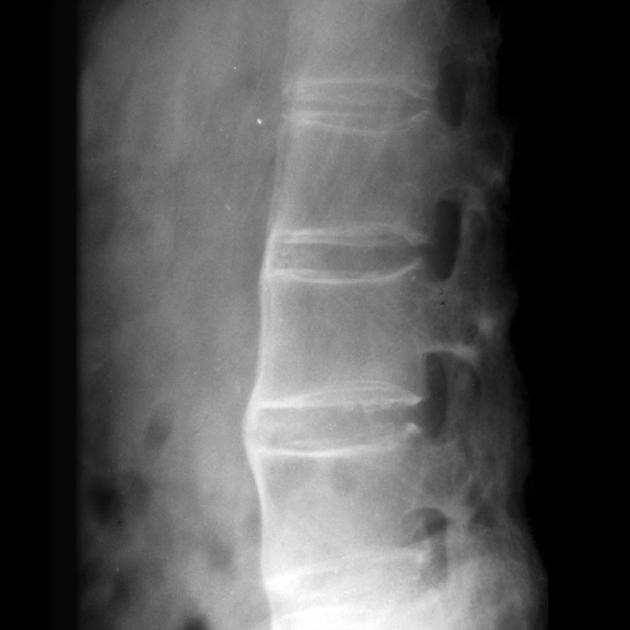

这个疾病主要影响脊柱和骨盆的关节,会导致慢性炎症和疼痛,严重时甚至会让脊柱变得僵硬弯曲

三、骨骼健康评估工具与方法

强直性脊柱炎患者的骨骼健康问题特别突出,不仅有炎症本身的影响,还有药物和活动受限等因素

评估骨骼健康就像给房子做结构检查,要从多个角度来看

1、骨密度检测技术应用